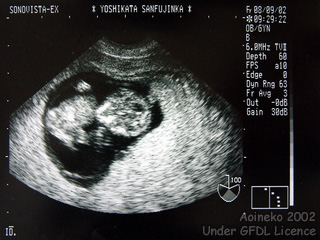

L'échographie est une technique d'imagerie utilisant des ultra-sons. En médecine elle est surtout connue pour donner une image du foetus dans le ventre de sa mère. On l'utilise également pour visualiser des organes (foie, coeur, etc.).

Echographie.   Auteur : Aoineko 2002